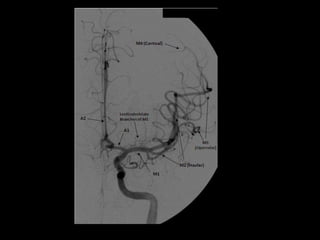

-Lateral 2D view following

selective external carotid

artery injection , there is a

hypervascular mass adjacent

to the proximal ECA, this is

the typical appearance of a

carotid body tumor (glomus

or paraganglioma)

6 occipital artery

9 lingual artery

10 facial artery

11 superficial temporal

artery

12 internal maxillary artery

13 middle meningeal

15 deep temporal artery